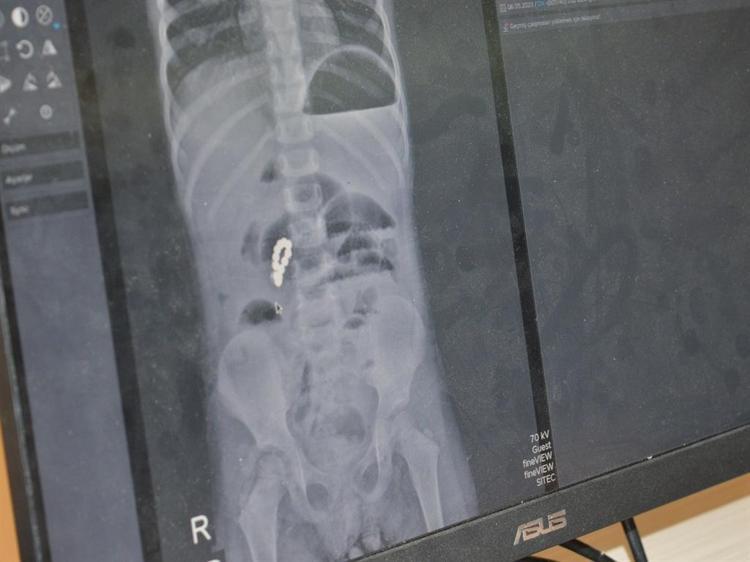

Burada Çocuk Cerrahi Uzmanı Op. Dr. Mürsel Haspulat tarafından ameliyata alınan Peker’in bağırsaklarında farklı zamanlarda yuttuğu 8 adet boncuk mıknatısın birbirine yapışarak bağırsakları deldiği ve tıkadığı belirlendi. Yaklaşık 3 saat süren ameliyatta bağırsaklar tek tek onarıldı, ameliyat sırasında tekrar röntgen çekilerek içeride başka parça kalıp kalmadığı kontrol edildi. Ağır geçen operasyonun ardından 6 gün yoğun bakımda kalan Peker, sağlığına kavuşarak taburcu edildi.

Ufak parçacıklı oyuncakların özellikle 6 yaşından küçük çocuklara verilmemesi gerektiği konusunda aileleri uyaran Op. Dr. Mürsel Haspulat, “Basit görünen bir oyuncak çocuğumuzu ölümle burun buruna getirdi. Bu tür mıknatıslar bağırsaklarda birleşerek hayati risk oluşturabiliyor. Aileler özellikle kış aylarında çocuklarını küçük ve parçalı oyuncaklardan, pillerden ve sert gıdalardan uzak tutmalı. 4 yaşındaki Eda, karın ağrısı ve kusma şikayetiyle geldi. Normalde basit bir şekilde apandisit ya da bağırsak düğümlenmesi diye düşünebildiğimiz bir vakaydı. Ama sonrasında röntgenlerini çekip hızlıca ameliyata almamız gereken bir durumla karşı karşıya kaldık. Çünkü ailenin de fark etmediği şekilde 2-3 hafta içinde tane tane mıknatıs parçalarını yutmuş ve bu mıknatıs parçaları bağırsakları birbirine yaklaştırarak düğümlenmesine ve delinmesine neden olup çocuğun bağırsaklarının tıkanmasına neden olmuştu. Ameliyatta öncelikli karmaşık tabloyu tek tek çözerek delinmiş bağırsak kısımlarını onardık. 3 saat boyunca uğraştık, devamında ameliyatın ortasında röntgen çektik tekrar içeride başka bir parçacık var mı diye kontrol ettik. Bir tane kalmıştı, onu da çıkartıp ameliyatı tamamladık. Fakat çok ağır bir ameliyat olduğu ve genel durumu da bozulmuş olduğu için çocuğumuz 6 gün boyunca yoğun bakımda yatmak zorunda kaldı. Yoğun bakımda 3’üncü gününde çok şükür beslenmeye başladı, daha sonra da servisi aldık. Şu anda taburcu ettik. Çok iyi ve şanslı bir vaka olarak sonuçlandı. Aileleri kesinlikle bu basit mıknatıslı oyuncaklar konusunda şiddetle uyuyorum. Farklı zamanlarda yutulduğunda ölümle burun buruna gelmesine neden olabiliyor. 6 yaş öncesi çocuklara parçacıklı oyuncaklar, madeni paralar verilmemeli. Bu ay çok fazla madeni para yutmalar geldi, yemek borusunda takılı kalıp yine ölümcül tablolara yol açabiliyorlar. Leblebi gibi parçacıklı gıdaları bile ailelerin 6 yaşından küçük çocuklara vermemeleri gerekiyor” diye konuştu.